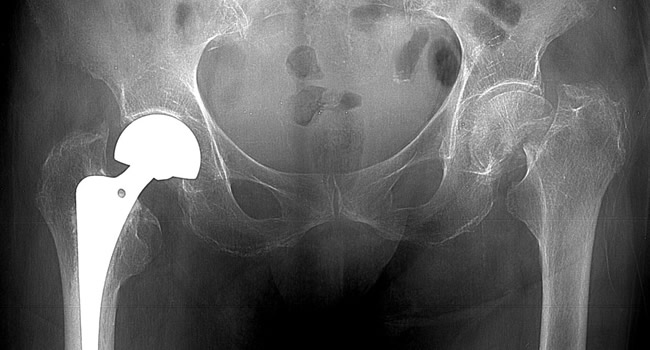

Οι ακτινογραφίες πραγματοποιούνται με πλήρως ψηφιακό εξοπλισμό και όχι ψηφιοποιημενο από έμπειρους Τεχνολόγους – Ακτινολόγους με άδεια ασκήσεως Επαγγέλματος.

Ο πιο σύγχρονος φορητός Ακτινολογικός εξοπλισμός πλήρως ψηφιακής απεικόνισης (DR) σε μια κινητή ακτινολογική μονάδα, μπορεί να επισκεφθεί τον ασθενή οπουδήποτε στην περιοχή της Θεσσαλονίκης και των περιχώρων και να σταλεί, αν ο ασθενής το επιθυμεί, η γνωματευμένη ακτινογραφία ηλεκτρονικά μέσω διαδικτύου στον θεράποντα- παραπέμποντα ιατρό ο οποίος θα λάβει το αποτέλεσμα στο προσωπικό του υπολογιστή, tablet, Smartphone οπουδήποτε κι αν βρίσκεται.

Ο ασθενής που δεν πρέπει ή δε μπορεί να μετακινηθεί, από τον χώρο του, επωφελείται από υπηρεσίες ίδιες με αυτές που προσφέρονται σε ένα σταθερό ακτινολογικό εργαστήριο ελαχιστοποιώντας το κόστος αφού δεν επιβαρύνονται με έξοδα μετακίνησης.